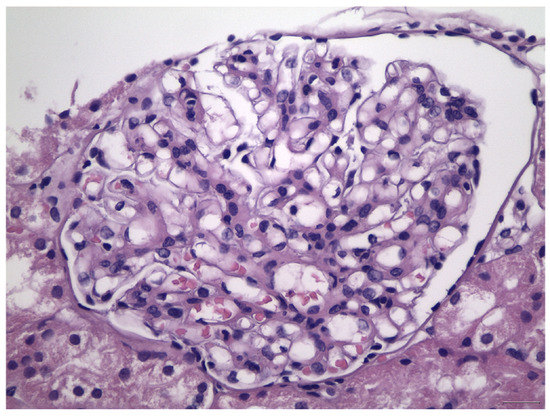

- Haas, M. Histologic subclassification of IgA nephropathy: A clinicopathologic study of 244 cases. Am. J. Kidney Dis. 1997, 29, 829–842. [Google Scholar] [CrossRef]

- Cattran, D.C.; Coppo, R.; Cook, H.T.; Feehally, J.; Roberts, I.S.D.; Troyanov, S.; Alpers, C.E.; Amore, A.; Barratt, J.; Berthoux, F.; et al. The Oxford classification of IgA nephropathy: Rationale, clinicopathological correlations, and classification. Kidney Int. 2009, 76, 534–545. [Google Scholar] [CrossRef] [PubMed]

- Roberts, I.S.D.; Cook, H.T.; Troyanov, S.; Alpers, C.E.; Amore, A.; Barratt, J.; Berthoux, F.; Bonsib, S.; Bruijn, J.A.; Cattran, D.C.; et al. The Oxford classification of IgA nephropathy: Pathology definitions, correlations, and reproducibility. Kidney Int. 2009, 76, 546–556. [Google Scholar] [CrossRef] [PubMed]